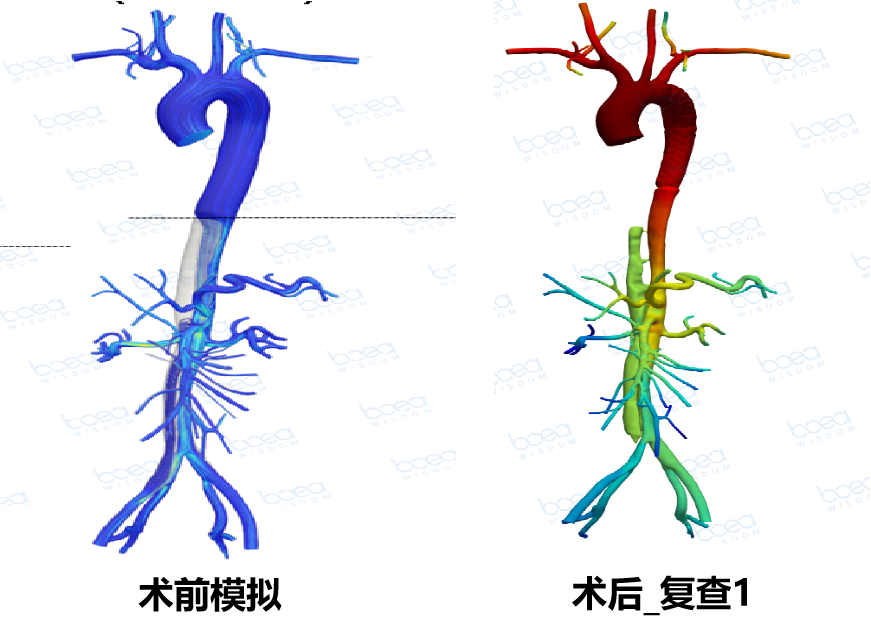

本次大会期间,浙江大学医学院附属第二医院陈兵教授与各位专家同道分享讨论了《术前规划对主动脉夹层治疗的影响》。陈兵教授以一个具体病例介绍了术前规划如何帮助医生制定手术方案,并通过术前模拟和术后随访来验证术前规划的有效性。欢迎阅读。

根据体外模拟演示和临床可选择支架情况,判定28mm支架对真腔重塑,远端血流动力学恢复效果最佳,决定植入直径28mm,长度160mm胸主动脉支架

根据术前规划进行的手术快捷而稳定,过程顺利,效果满意。

1. 血管重塑验证:术后复查显示真腔恢复与术前规划预测一致,验证了术前规划的有效性。

术后_复查1